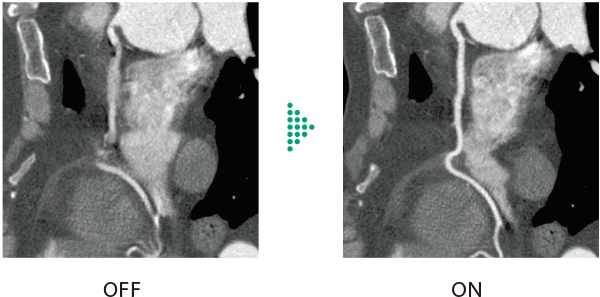

心臓CT検査で画像のブレを抑える

従来の心臓CT検査*2 は、高心拍や不整脈など撮影中の心拍数変化により心臓全体の画質に影響を与えることがありました。Cardio StillShotは、収集したRawDataから被写体の動く方向と量を4次元的に算出し、動きによるブレの少ない画像を提供します。画像再構成時に補正を行うことで、最高28msecの実効時間分解能*3 を実現します。

- *2 SCENARIAの場合

- *3 0.5秒スキャン、心拍数80bpm以下の場合